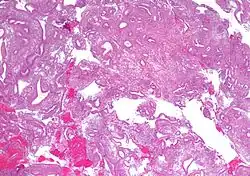

Micrograph showing simple endometrial hyperplasia, where the gland-to-stroma ratio is preserved but the glands have an irregular shape and/or are dilated. Endometrial biopsy. H&E stain.

Like other hyperplastic disorders, endometrial hyperplasia initially represents a physiological response of endometrial tissue to the growth-promoting actions of estrogen. However, the gland-forming cells of a hyperplastic endometrium may also undergo changes over time which predispose them to cancerous transformation. Several histopathology subtypes of endometrial hyperplasia are recognisable to the pathologist, with different therapeutic and prognostic implications.[4]